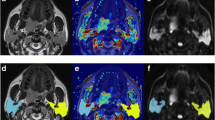

From pre-RT to post-RT, the volume of bilateral parotid glands significantly decreased from 26.1 ± 5.5 cm3 to 18.9 ± 3.9 cm3, with an atrophy rate of 26.5 ± 10.3 % (p < 0.001). The pre- and post-RT IVIM and DCE MR images of the bilateral parotid glands in one representative NPC patient are shown in Fig. 2.

MR images of bilateral parotid glands (arrows) in one patient with nasopharyngeal carcinoma (NPC). a-h Dynamic contrast-enhanced (DCE, a-d) and intravoxel incoherent motion (IVIM, e-h) MR images within 2 weeks before radiotherapy (pre-RT). i-p DCE (i-l) and IVIM (m-p) MR images approximately 4 weeks after radiotherapy (post-RT). At pre-RT, the right and left parotid maximum relative enhancement (MRE, b), time to peak (TTP, c), Wash in Rate (d), apparent diffusion coefficient (ADC, e), pure diffusion coefficient (D, f), perfusion fraction (f, g), and pseudo-diffusion coefficient (D*, h) values are 222.8 and 243.7 %, 46.8 s and 52.0 s, 143.9 i/s and 100.7 i/s, 0.76 × 10−3 mm2/s and 0.85 × 10−3 mm2/s, 0.69 × 10−3 mm2/s and 0.73 × 10−3 mm2/s, 0.089 and 0.116, and 50.8 × 10−3 mm2/s and 32.2 × 10−3 mm2/s, respectively. At post-RT, the right and left parotid MRE (j), TTP (k), Wash in Rate (l), ADC (m), D (n), f (o), and D* (p) values are 335.6 and 357.9 %, 62.6 s and 83.5 s, 237.0 i/s and 146.4 i/s, 1.70 × 10−3 mm2/s and 1.59 × 10−3 mm2/s, 1.41 × 10−3 mm2/s and 1.31 × 10−3 mm2/s, 0.184 and 0.175, and 54.3 × 10−3 mm2/s and 39.0 × 10−3 mm2/s, respectively